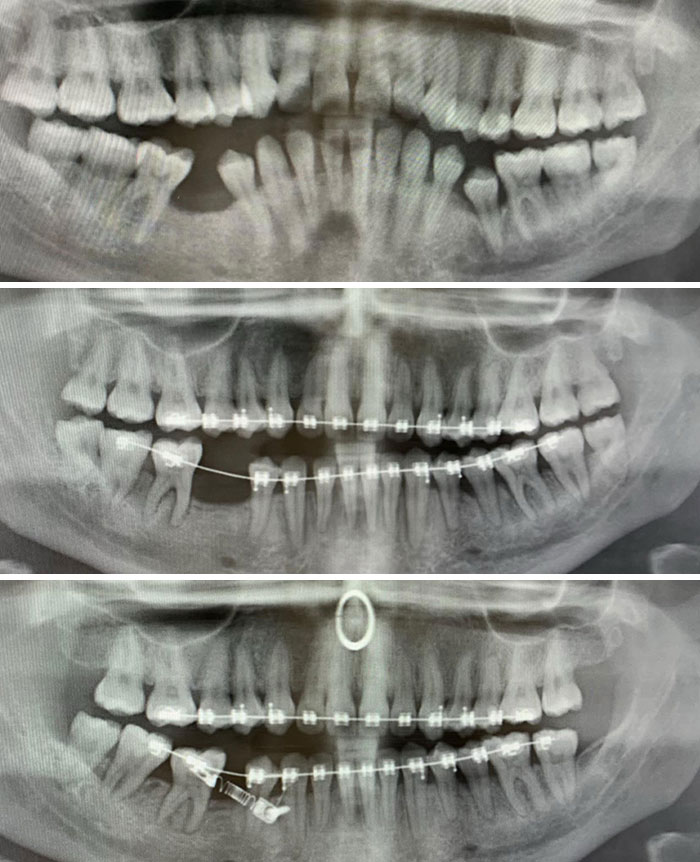

My X-Rays Before Braces In August 2018 To Now August 2020